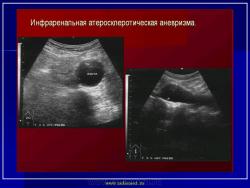

УЗИ  аорты.